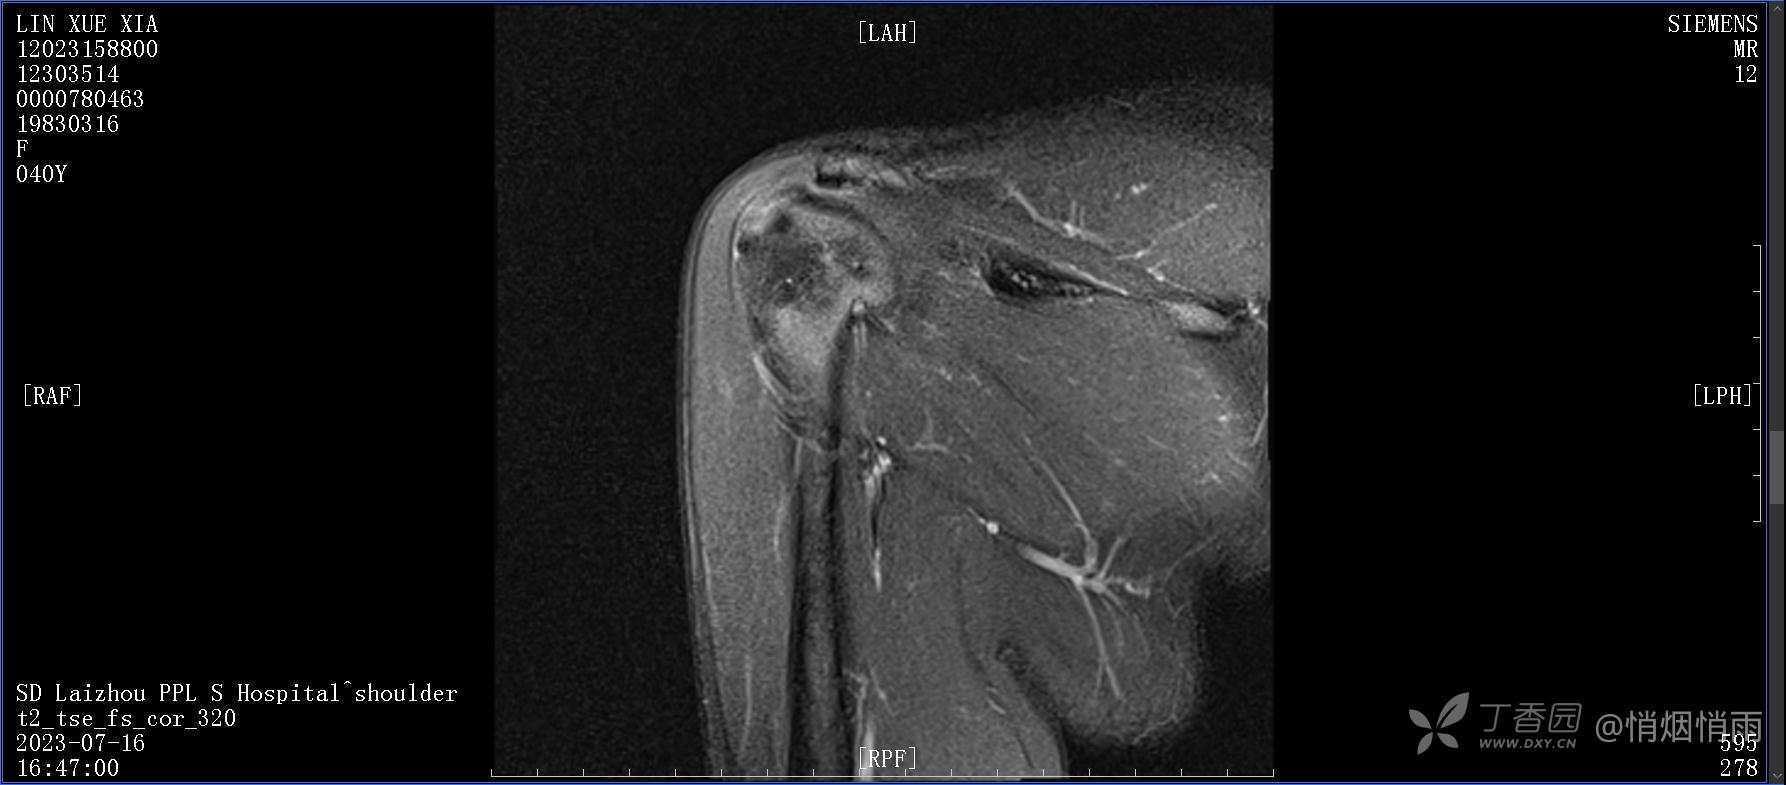

查体:右肩关节局部轻度肿胀,肩胛区压痛明显,痛处不固定,肩关节痛性活动受限,jobe test(+),lift -off test(+),中指、环指感觉较余指减退,余肢端感觉及血运情况可。

目前的诊断,暂时依据辅助检查诊为肩袖损伤,但是患者疼痛的性质和特点,却不是单纯的肩袖损伤所致。考虑过胸廓出口综合征,但是该疾病会出现肩胛区的疼痛吗?(由于考虑到费用的问题,没再进行下一步的检查)带状疱疹会有如此的症状吗?